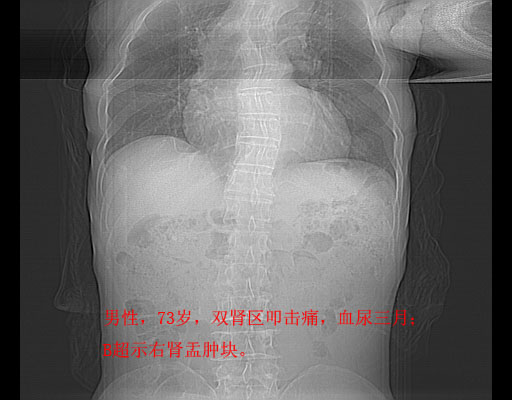

平扫

考虑右肾盂癌,肾动脉受侵,右肾功能减退,右肾盂输尿管积水,管壁增厚,考虑种植转移,应该把下面扫完的

支持右侧肾盂癌伴肾静脉瘤栓形成可能性大,右肾结石.肝右叶后段低密度影,不除外转移.

右肾盂旁ca并肾静脉瘤栓形成/肾功能降低。

右肾结石。

右肾盂癌,肾动脉受侵,右肾盂输尿管积水,管壁增厚,考虑种植转移

1.右侧肾盂癌伴肾盂积水。

2.肾脏功能减退,原因有:(1)肾动脉受侵。(2)肾静脉受侵(3)肾积水,等。本例,肾动脉显影较好,但受压明显;肾静脉无明显显示,受压或静脉癌栓,下腔静脉腔内未见明显充盈缺损。

3.右侧上段输尿管扩张,原因:(1)积水所致;(2)种植。